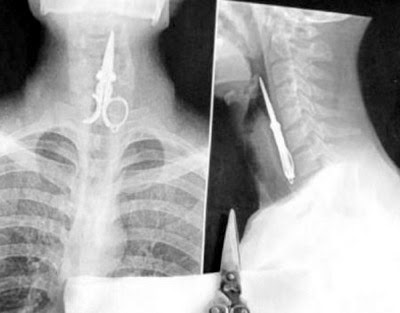

O forfecuţa întreagă în interiorul gâtului unui bărbat. :-s Cum or fi ajuns acolo.